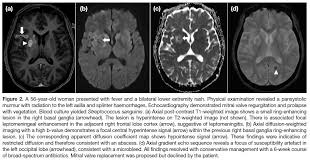

Delica Medical at European Stroke (ESOC) Munich - DELICA

Hong Kong Journal of Radiology